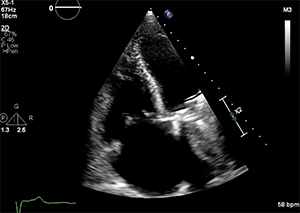

The patient’s left ventricular (LV) systolic function was mildly reduced (LV ejection fraction, 40%–45%), and he had a dilated right ventricle with mild systolic dysfunction based on standard normal ranges (Figure 1 and Figure 2). His right ventricular (RV) systolic pressure was estimated to be 56 mm Hg, as assessed by echocardiography. The results of right heart catheterization showed a pulmonary capillary wedge pressure of 19 mm Hg (V wave to 28 mm Hg), pulmonary artery pressure of 50/14 mm Hg (mean, 29 mm Hg), RV pressure of 50/14 mm Hg, and right atrial pressure of 15 mm Hg (V wave to 20 mm Hg).

Transthoracic and transesophageal echocardiography (TEE) confirmed severe functional TR due to annular dilation associated with RV and right atrial enlargement. Mild leaflet tethering, predominantly septal, was also appreciated. The coaptation gap was < 10 mm and the jet origin was predominantly central with extension toward the anteroseptal commissure. Image quality in both transesophageal midesophageal and transgastric windows were good (Videos 1–5).